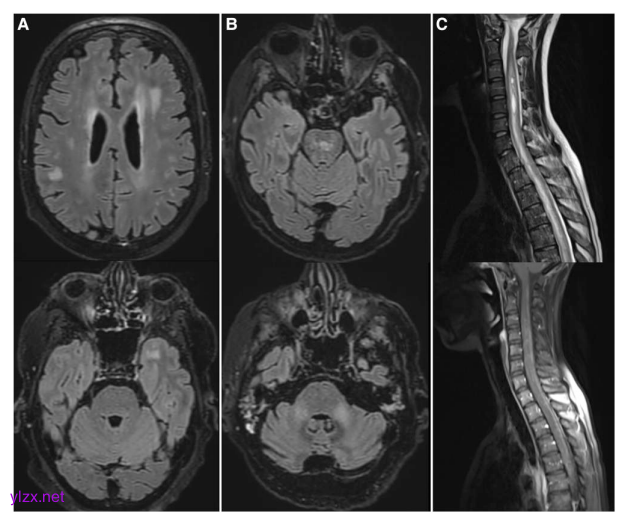

这项研究详细分析了患者的临床表现,结果令人担忧。最常见的症状包括认知功能障碍(41%)、肢体无力(21%)、意识障碍(20%)、感觉异常(18%)和头痛(15%)。值得注意的是,无论是移植后早期(100天内)还是晚期(100天后)发病的患者,临床表现都没有显著差异。在影像学检查方面,MRI的检出率明显高于CT,57%的患者MRI发现了与临床症状相符的异常表现,而CT的检出率仅有7%。更令人关注的是,所有发现脊髓MRI异常的7例患者都是在移植100天后发病的。